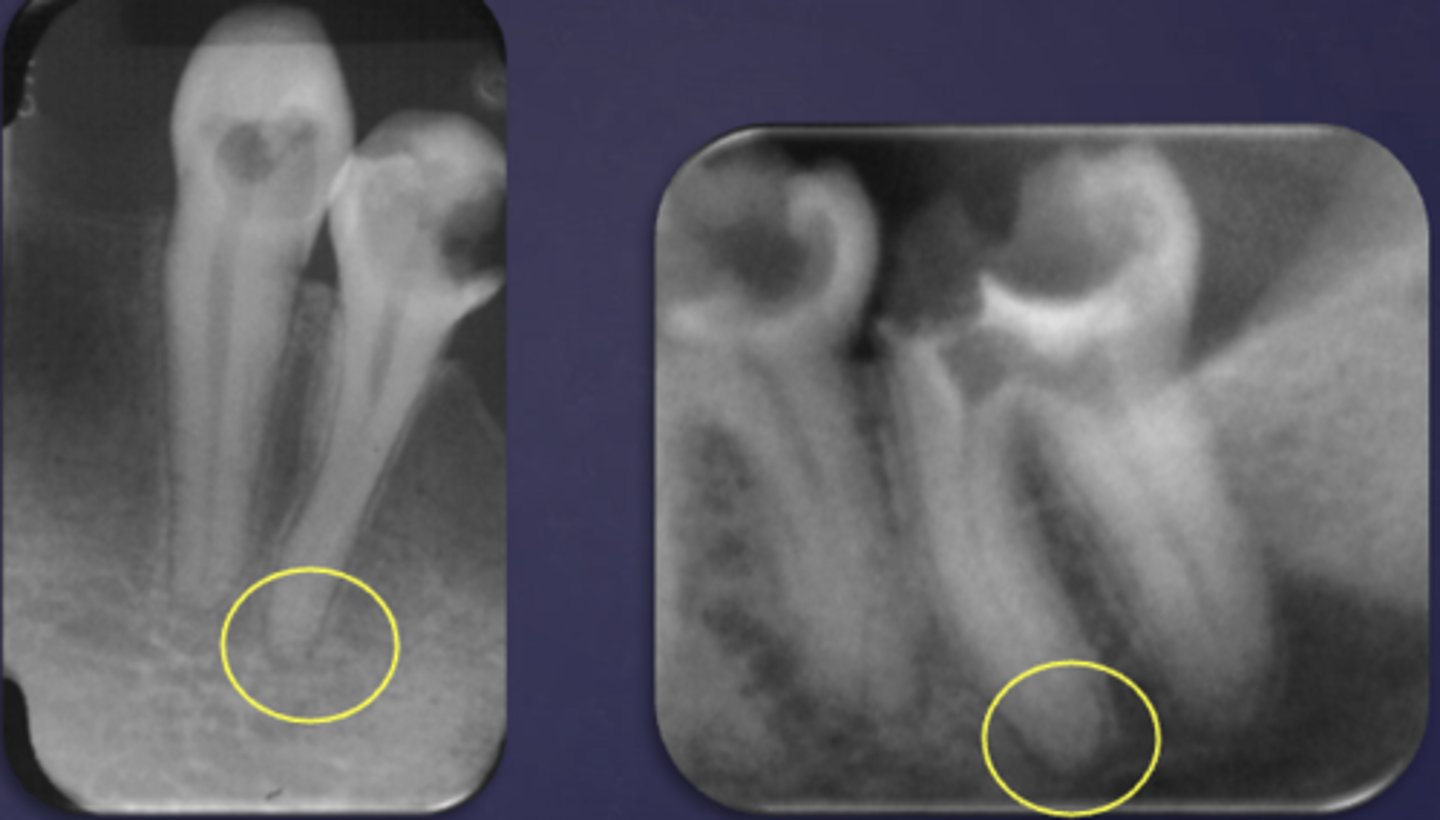

What are two defects that the arrows are pointing to?

- Widened PDL

- Sclerosis

What type of change is seen in this radiograph?

early change (apical periodontitis #30)

early change (apical periodontitis #21)

early change (apical periodontitis #17-18)

early change (apical periodontitis #14)